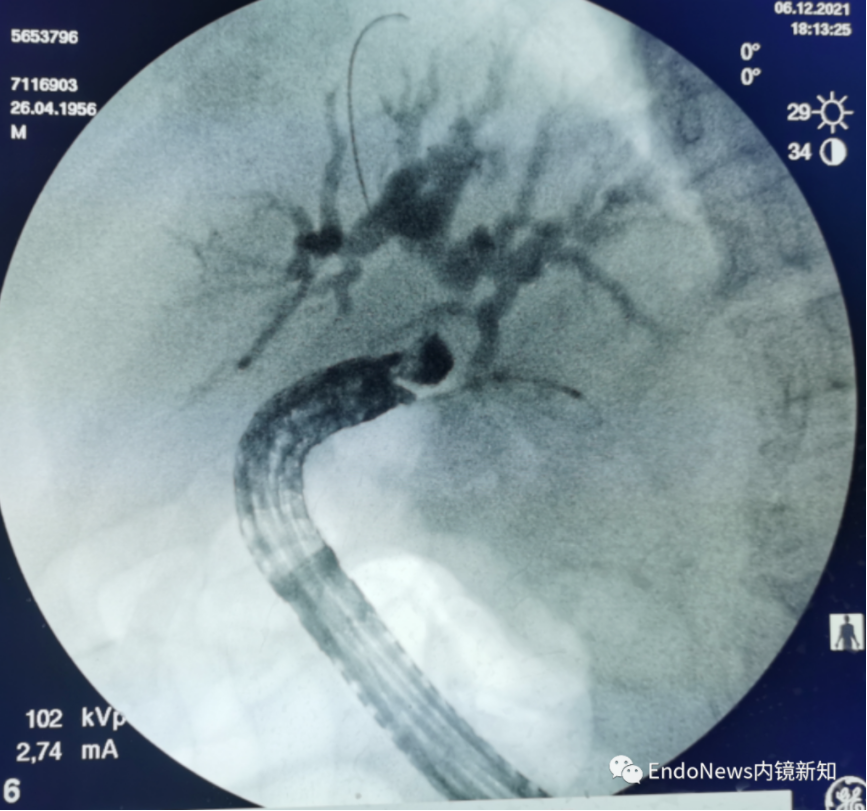

如图a所示,导丝到达胆总管的位置,这时胆总管已经显影,我们的目标是进行顺行操作。

导丝进胆总管之后,一直位于胆总管中下段,并且在这个位置调头回返了,其实我们看造影,这个位置应该是胆总管本身有一个弯折,造成导丝到这个位置后总是打弯。

如图(b)中所示,尝试好几次,导丝一直往上返,而并不往胆管下游方向走。这时可考虑使用囊肿切开刀辅助,囊肿切开刀是直的,而导丝也是直的,可以将导丝顺下来到达如图(c)中所示位置。